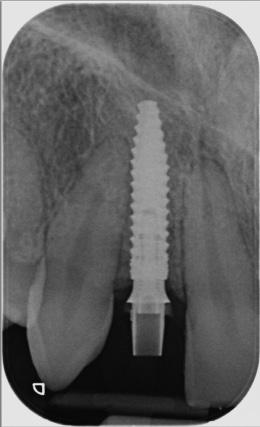

CASE STUDY

Guided implant approach for reproducible results, page 28